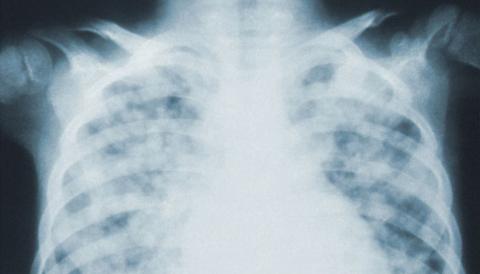

The researchers found that a pre-trained neural network called DarkNet-19 can rapidly and reliably detect COVID-19 on chest X-rays. The network recognized the disease’s imaging patterns on nearly 6,000 chest X-rays with 94 per cent accuracy, outperforming 16 other available networks.

“In the earliest stages of COVID-19, chest X-rays often appear normal to the naked eye,” says Savvas Nicolaou, the senior author of the study and the director of emergency and trauma imaging at Vancouver General Hospital. “But in the right clinical context, applying AI-augmented analysis to the same images may reveal the subtle presence of the disease.”